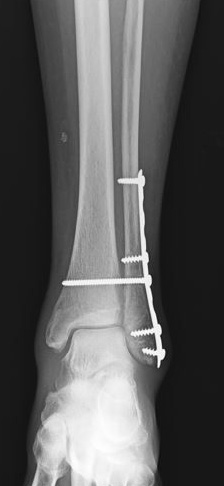

internal fixation of ankle fracture

A broken bone in this patient’s ankle is held in position with plates and screws.